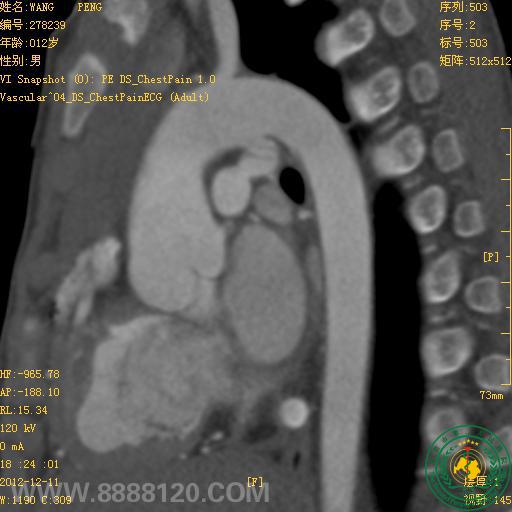

我院炫速双源CT正式投入使用第二周,今天即对1例高心率(114次/分钟)法洛氏五联症合并动脉导管未闭患者作了心脏、冠状动脉、主动脉和肺动脉检查,一次扫描,快速、准确诊断。

1.右心室增大,室间隔干下部缺损,房间隔卵圆孔缺损,主动脉骑跨室间隔,肺动脉主干和右室流出道狭窄,诊断为法洛氏五联症,双侧下肺动脉明显加宽。

2.主动脉弓和肺动脉主干间见通道,诊断为动脉导管未闭。

3.左、右冠状动脉未见异常。